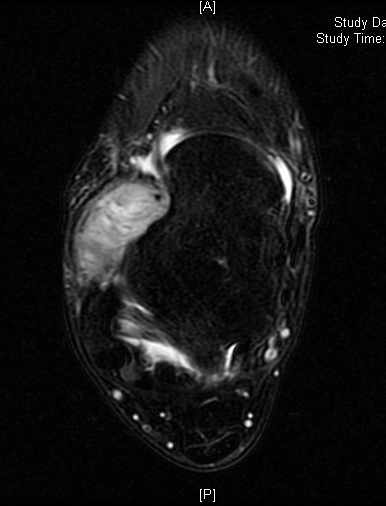

MRI

Shows multiloculated, heterogeneous mass.

“Triple Signal Intensity sign”; hypointense, isointense and hyperintense with fat on T2 – weighted MRI imaging. This sign is present in 30 to 50% of the cases. (Fig.3)

Under contrast enhancement Synovial Sarcoma appears heterogeneous and demonstrate areas of nodular enhancement.

In approximately 30% of cases a multiple vascular cannel may be identified

Synovial sarcomas may have a cystic appearance and are often mistaken for ganglion cysts especially those adjacent to tendons and in the foot and ankle.